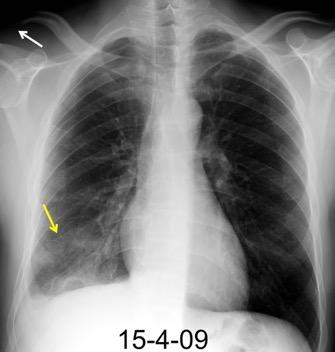

Neumonía a neumococos base izda. con derrame que aumenta.

Broncograma en lateral y en US.

(36-66% en ingresados)